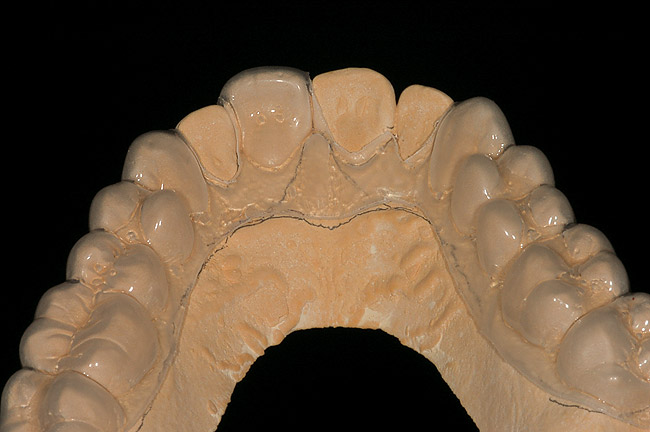

The ideal bleaching tray is fabricated on a horseshoe-shaped cast with no vestibule to provide good adaptation of the bleaching tray material. Also, the cast should be trimmed such that the central incisors are vertical to avoid folds on the facial. One challenge in fabrication of the single-tooth or regular bleaching tray is trimming the cast without abrading either the teeth or the gingiva. This outcome is accomplished by trimming the cast from the base rather than the sides (Figure 5).

Figure 5  Trimming the cast only from the base (with the central incisors horizontal) until the vestibule is removed and a hole occurs in the palate will avoid the danger of damaging teeth from traditional trimming as well as create the best cast for use in a vacuum-former.

Figure 5